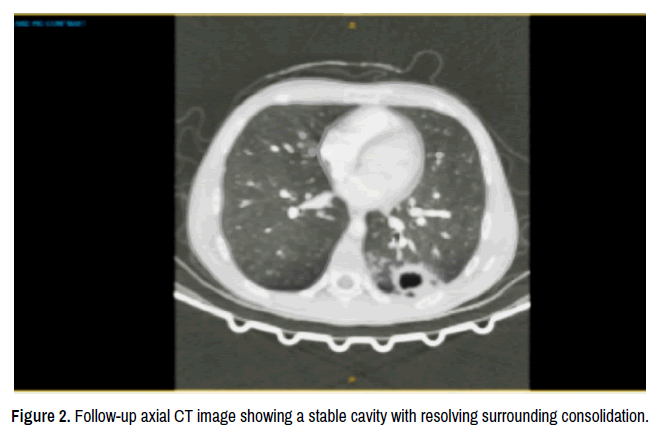

Laboratory investigations demonstrated a white cell count of 11.8 × 10⁹/L with neutrophilia, a C-reactive protein of 63 mg/L, a haemoglobin of 100 g/L, hypoalbuminaemia at 32 g/L and mild derangement of liver enzymes. Blood cultures remained negative. Imaging with computed tomography pulmonary angiogram ruled out pulmonary embolism but showed left lower-lobe consolidation with gas lucencies (Figure 1). A subsequent CT chest confirmed a thick-walled cavitary lesion measuring 58 × 58 × 36 mm with an air-fluid level. Thoracic ultrasound confirmed a loculated fluid-gas collection without pleural effusion. Sputum culture revealed mixed oral flora including anaerobes. A follow-up CT after one week demonstrated a stable cavity with no interval enlargement or pleural involvement (Figure 2).

Figure 1. Axial CT image demonstrating a thick-walled cavity with an air–fluid level in the left lower lobe, consistent with a lung abscess.